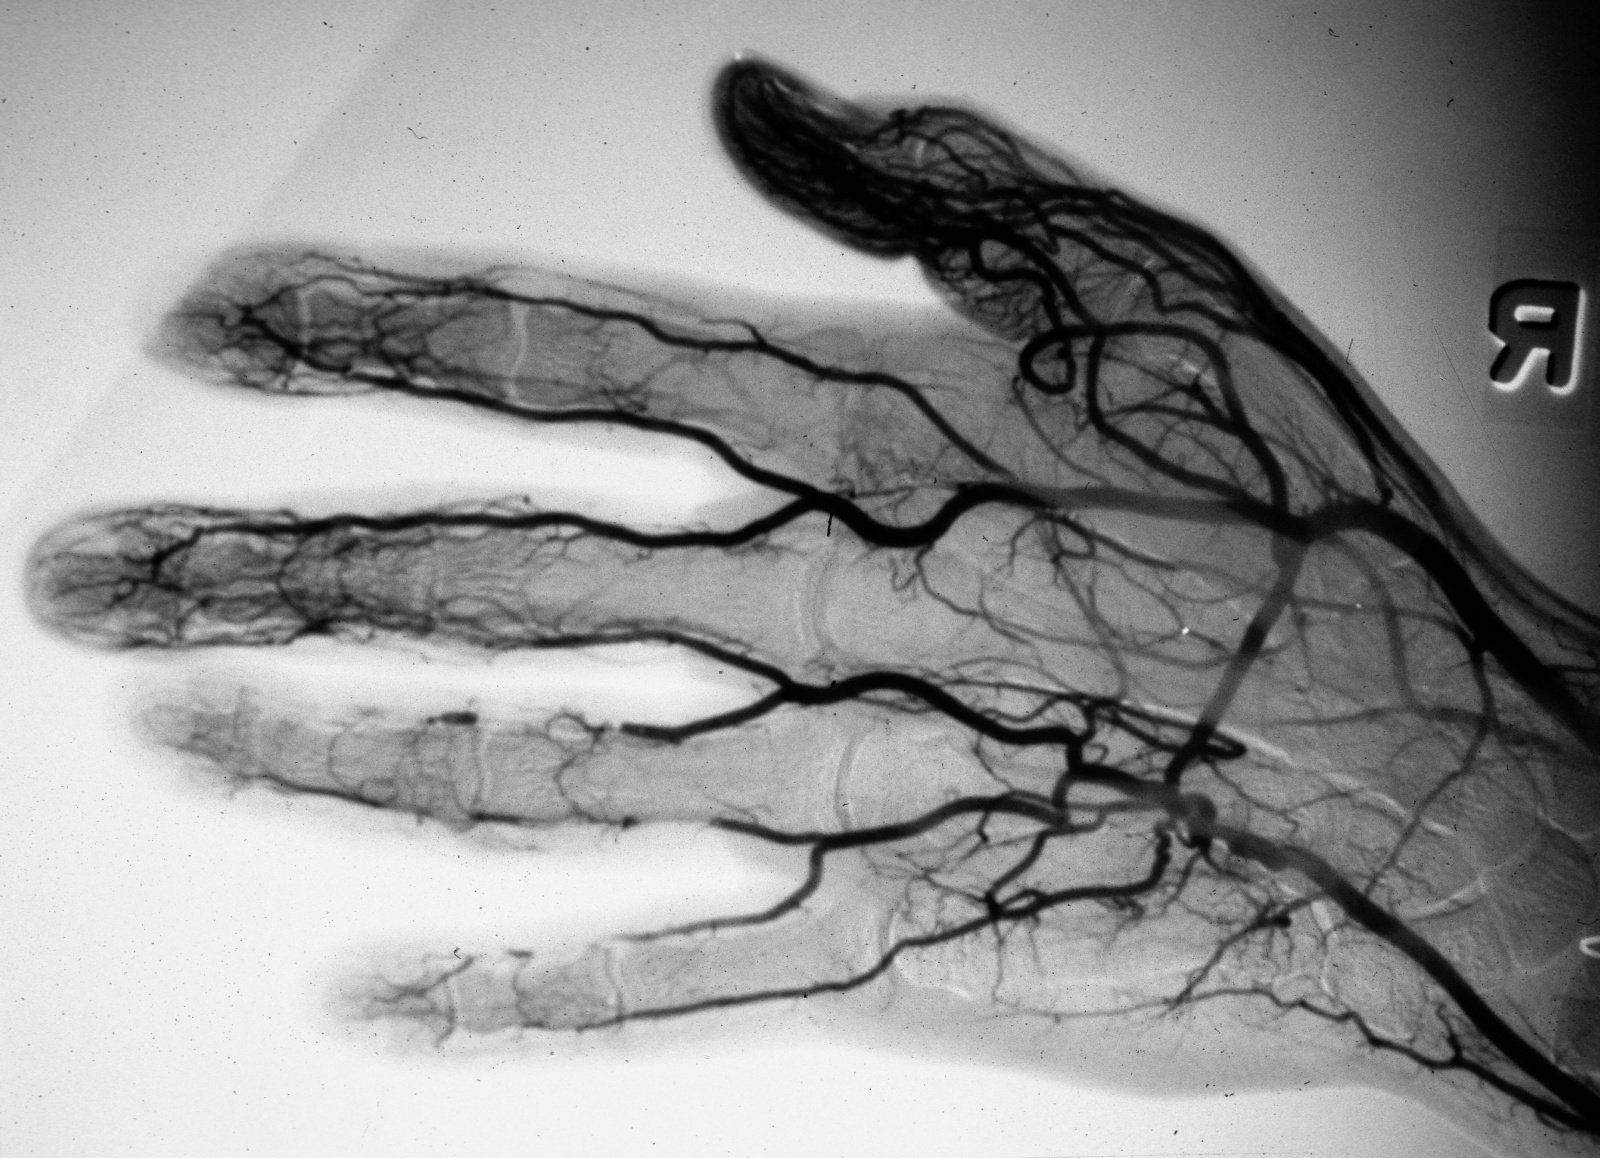

An arteriogram demonstrated partial blockage of the ulnar artery in the palm consistent with a partially occluded ulnar artery aneurism.

It also showed segmental digital artery occlusion suggestive of tiny emboli in the middle, ring and small fingers.